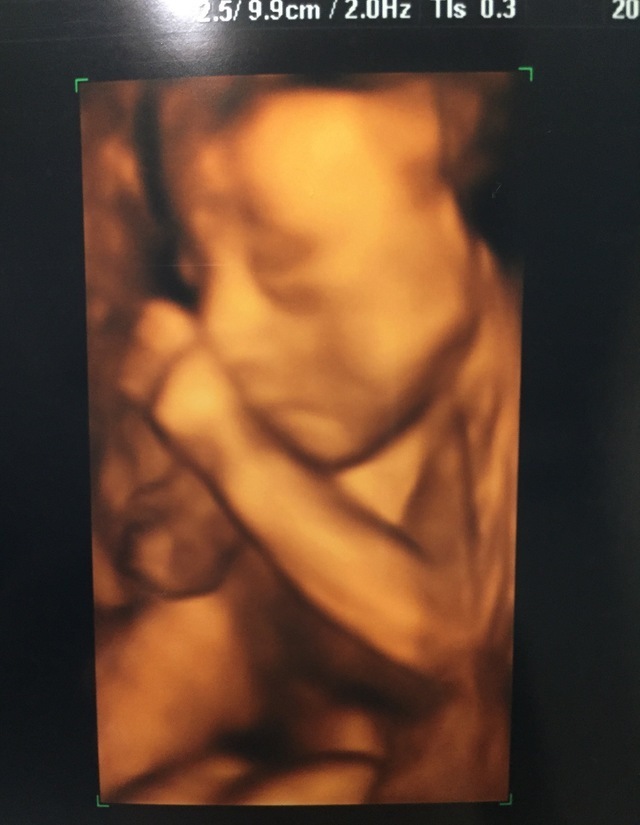

23週4日(23w4d・女の子)|amimin さん(27歳)

エコー写真撮影時のエピソード:

安定期もすぎて、赤ちゃんの骨格やお顔にもお肉がついてきて人間らしくなってきた頃のエコー写真です。

このエコー写真は、小さなかわいいおててでお鼻の上の部分を触っている写真で、主人と「考える人みたいだねー。」 と話してました。 お腹の中で何を考えていたのかなぁ。生まれた今もたまにこのポーズをします!